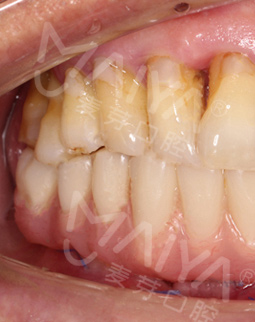

忙碌了大半辈子,终于可以退休享享清福。我和每个退休老人一样,每天就是接送孙子上下学,晚饭后和一群老友散散步,下下棋,日子过得清闲又自在。然而,平静惬意的生活却因为自己满口牙齿松动而“黯然失色”,不想出门,整天闷在家里看电视,后来牙齿问题严重的时候甚至把手机给停掉了。

要说我的牙齿问题,得从五年前说起,那时候因为对缺牙的不重视导致满口牙都受到影响,逐渐掉落,去年在不得已的情况下按照了假牙。但没想到,自从安装假牙后我连一点硬东西都吃不了,很多美食都无法享受,最主要的是卡环的钩子导致我张口就感到疼痛,这个假牙没用两三次就扔掉了。不由感叹一声,本来想要在退休后感受一下慢生活,谁知道连基本的饮食都成了问题。

麦芽的博士专家团在看过我的片子后发现,我的牙齿由于长期对口腔疏于护理,牙周情况非常差,余牙有些松动,且牙槽骨萎缩严重,现存的骨量无法进行传统的种植牙手术,因此给我设计了“all-on-4”种牙技术的升级版本“all-on-5”,前期是要处理我的牙周问题,当天就给安排了洁牙,然后上药,等牙周恢复差不多就可以进行种植了!